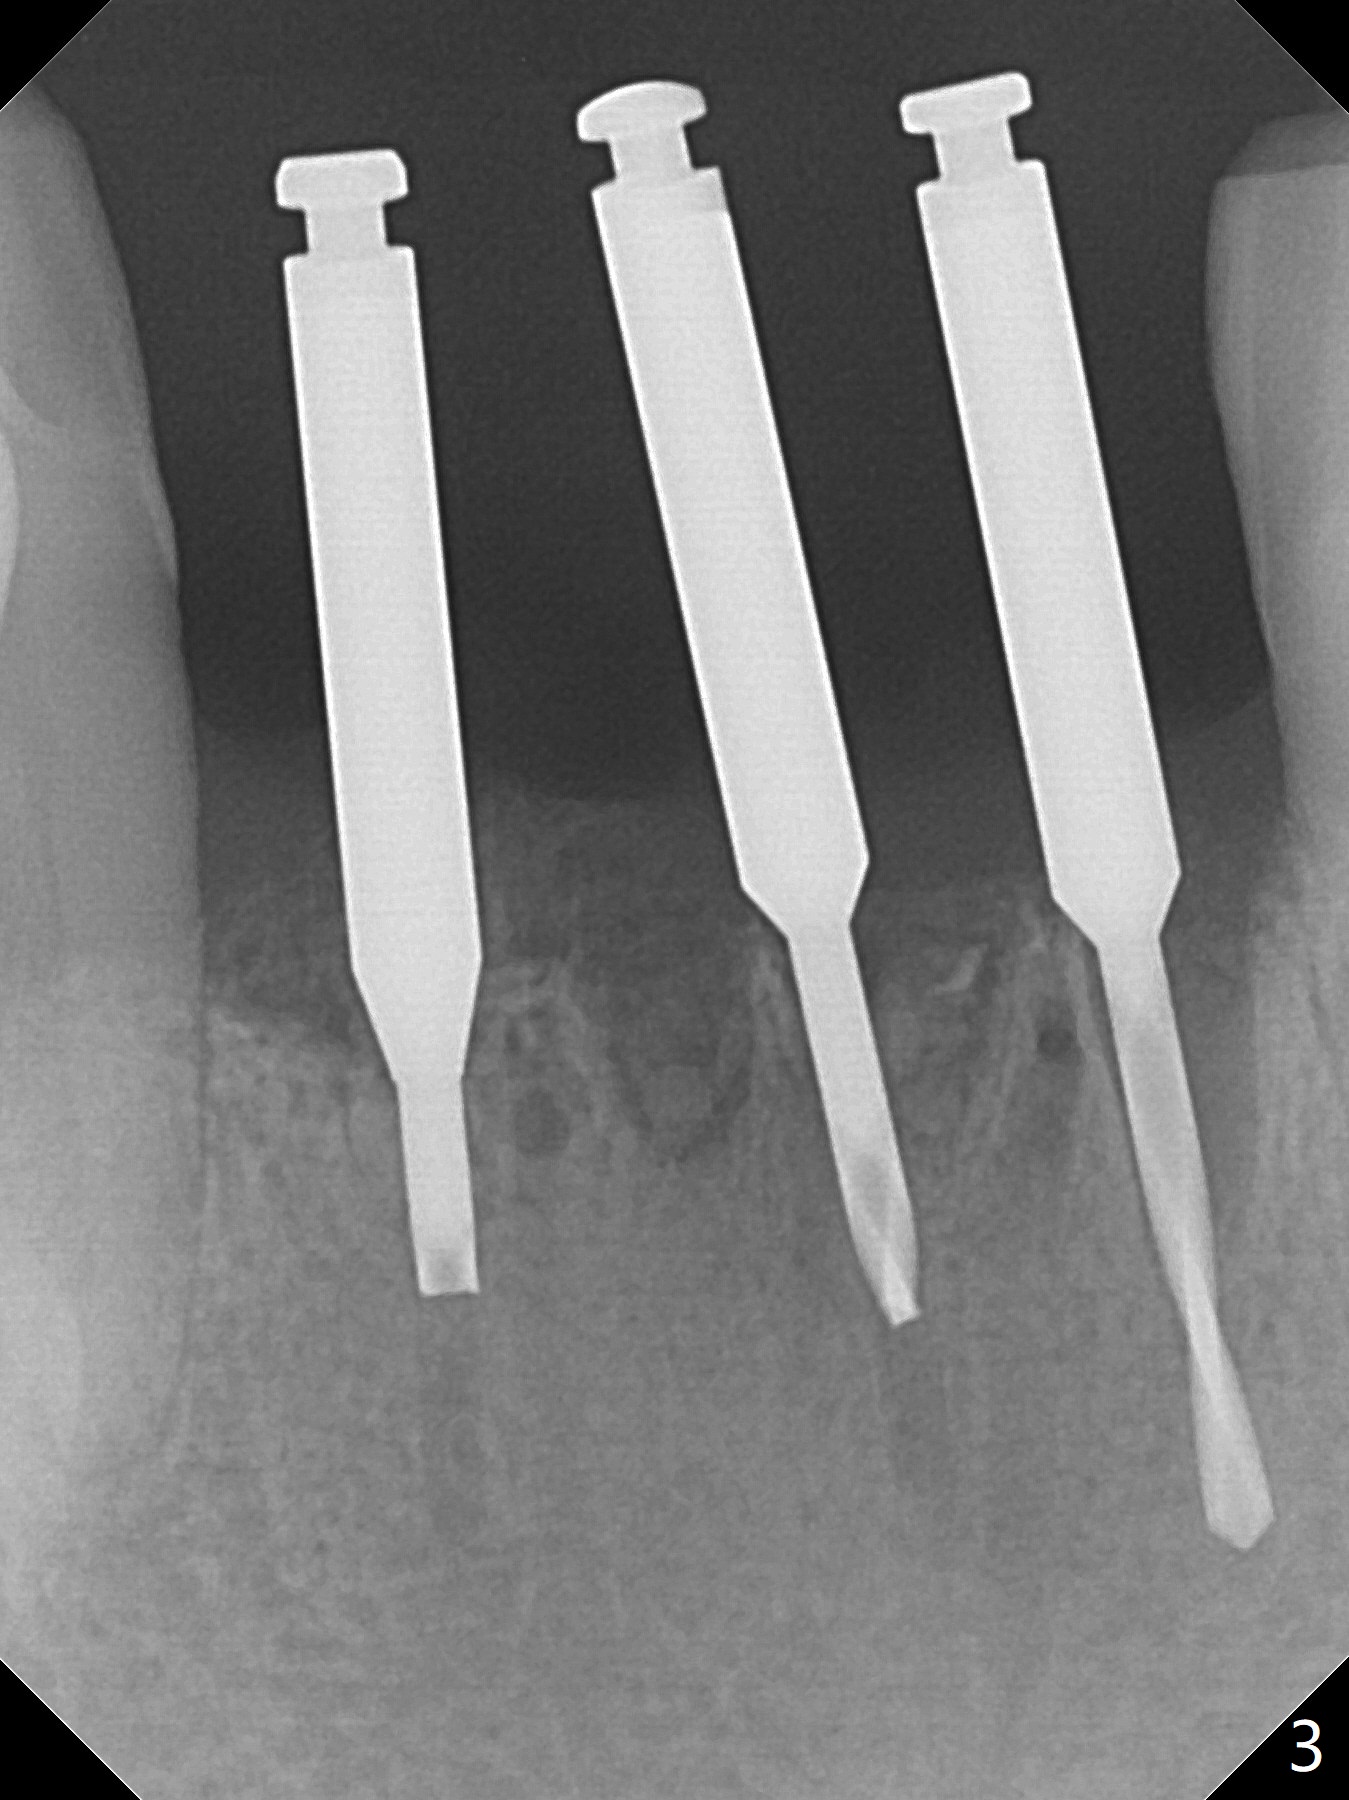

When the patient returns, the tooth #24 has exfoliated, while the ones at #25 and 26 has mobility III (Fig.1). The patient requests the tooth #23 extraction (Fig.2), but not #27. After SRP and extraction, osteotomy is initiated mesial to the sockets #23,25 and 26 (Fig.3,4) with intention to place 3 1-piece implants for 3 incisor crowns (Fig.5,6). Following Vanilla graft (Fig.5 *) a splinted provisional is fabricated to close the sockets (Fig.6). Peri-implant spaces close 5.5 months postop (Fig.7). Impression is taken after reprep for margin and parallelism (Fig.8). The final restoration consists of #23 single unit crown and #24-26 3-unit FPD (Fig.9). It appears that 2.5 mm 1-piece implants are not too small for the lower incisors (Fig.10-12), especially the central one (Fig.11). There may be perforation in the apical half of the lingual plate (L in Fig.10). The patient is not pleased with the shade of the #24-26 3-unit FPD (Fig.13 (6 months post cementation)). There is metal show through the abutments (*).